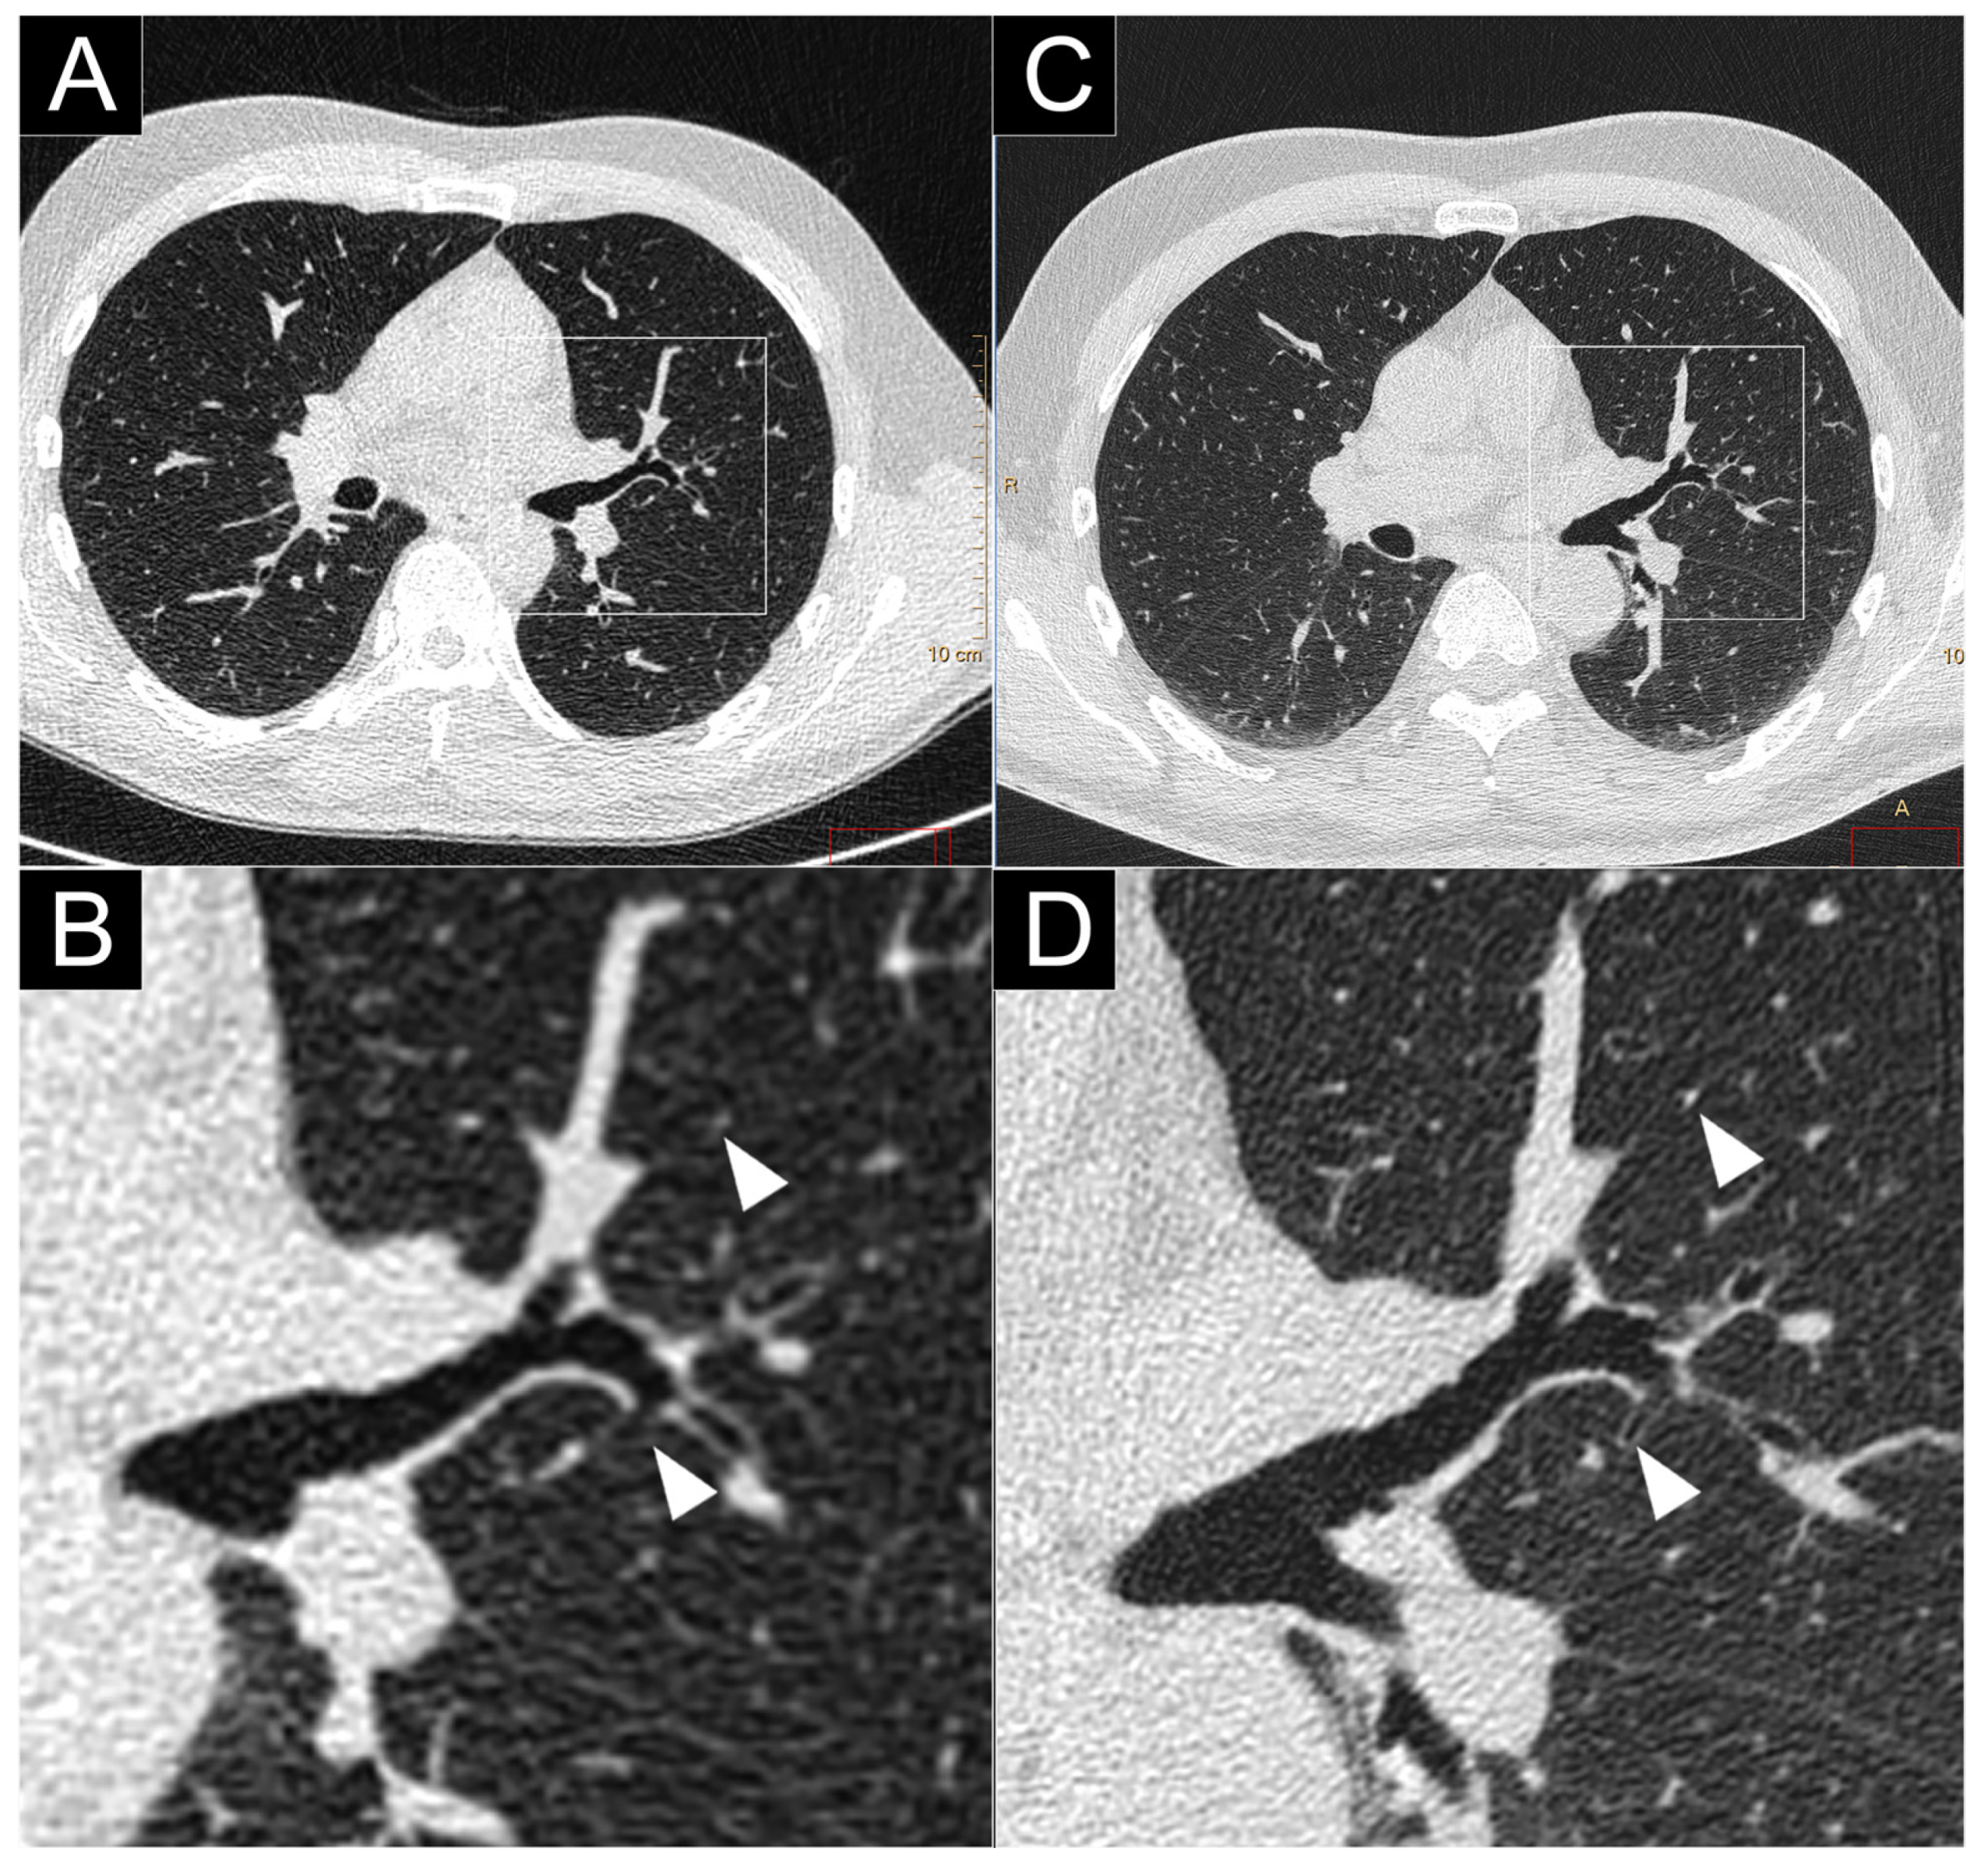

2.2.1. Spatial Resolution

- Bartlett, D.J.; Koo, C.W.; Bartholmai, B.J.; Rajendran, K.; Weaver, J.M.; Halaweish, A.F.; Leng, S.; McCollough, C.H.; Fletcher, J.G. High-Resolution Chest Computed Tomography Imaging of the Lungs: Impact of 1024 matrix reconstruction and photon-counting detector computed tomography. Investig. Radiol. 2019, 54, 129–137. [Google Scholar] [CrossRef]